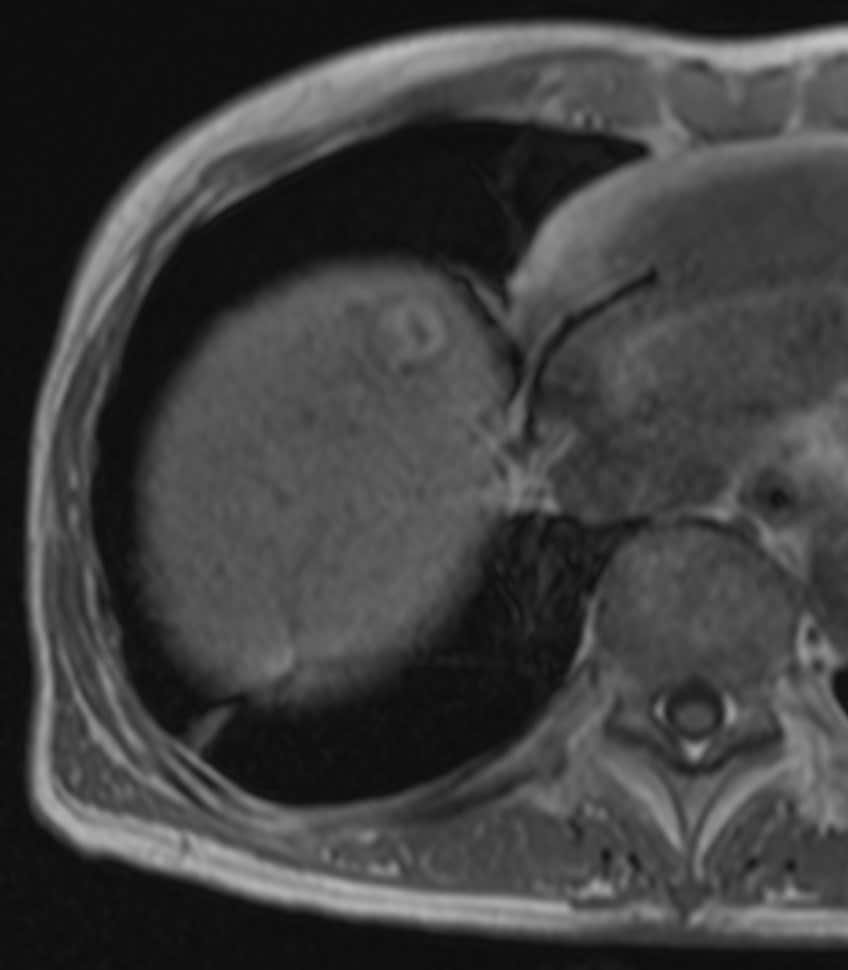

60歳代、女性、53kg、HCC

C型肝炎でフォロー中に肝腫瘍の指摘あり。前医CTにて肝内胆管癌が疑われ、手術目的に当院紹介。肝腫瘍の術前精査目的に再度造影CTとEOB-MRIを施行した。

Necrotic HCCと診断され、切除術を施行された。病理診断でも No residual carcinoma with necrosisとの診断であった。その後再発を認めず、経過観察となっている。

C型肝炎でフォロー中に出現した肝腫瘤について、前医CTではiCCが疑われたが、EOB-MRIにてNecrotic HCCが疑われた。肝切除を施行し、病理学的にもNecrotic HCCが証明された。EOB-MRIは,肝腫瘍の質的診断において有用であることが、あらためて確認された。